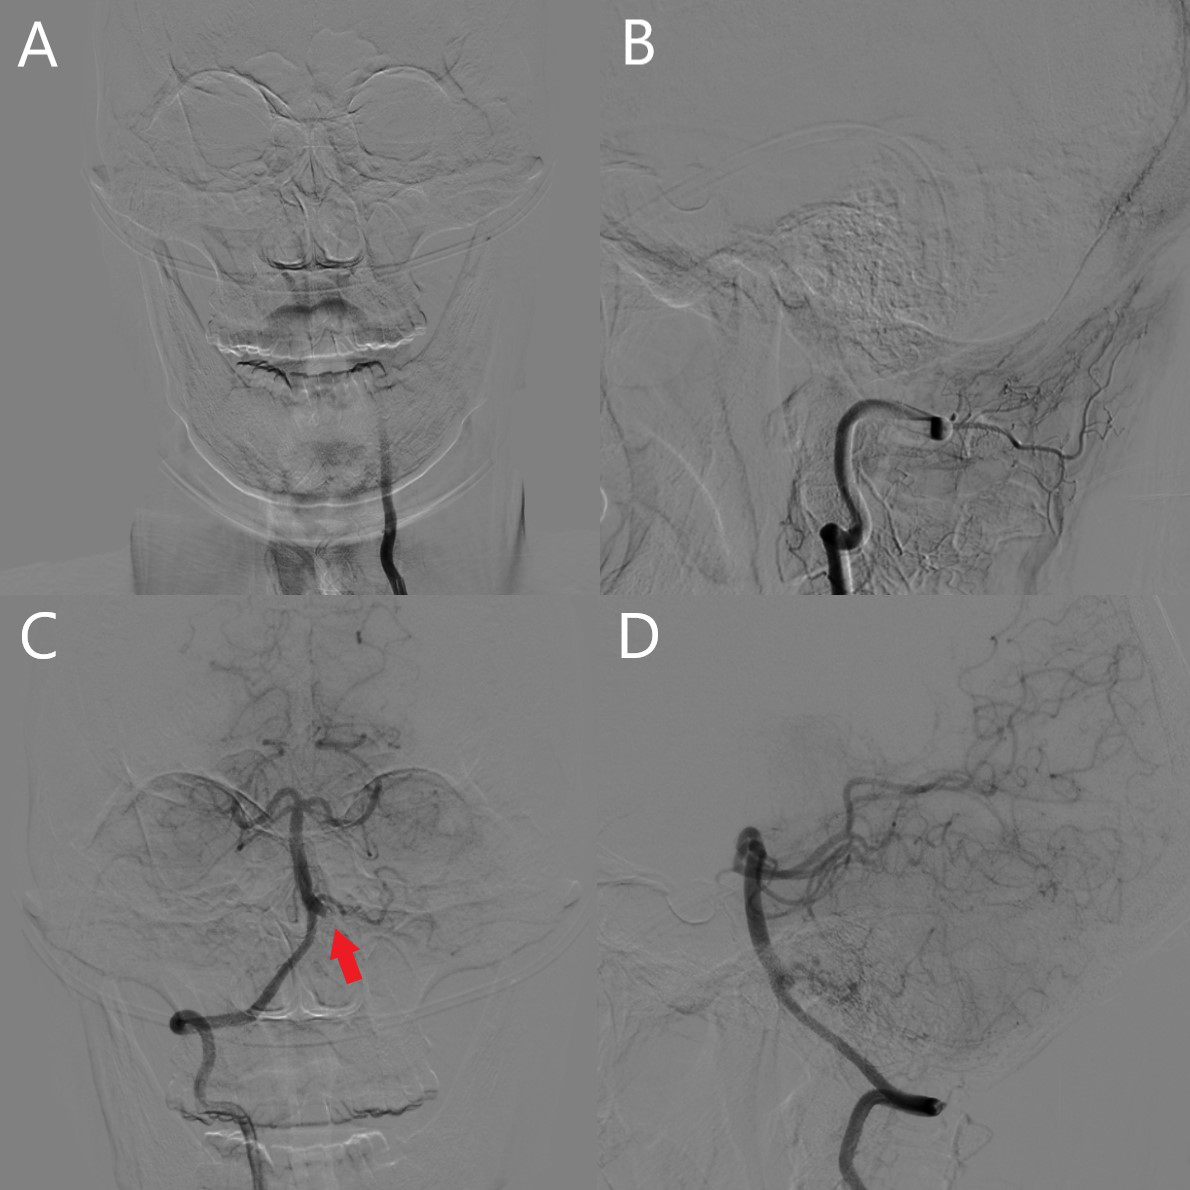

患者平卧DSA床,局麻成功后,用碘伏常规消毒手术区皮肤,铺无菌巾单。取右侧股动脉为穿刺点,Seldinger法穿刺成功后置入25cm 6F鞘。行经皮选择性脑血管造影见左侧椎动脉急性闭塞,左侧小脑后下动脉无显影,左侧小脑前下动脉由右侧椎动脉反流代偿,右侧椎动脉通畅,并且未见脊髓前动脉发出,基底动脉,双侧大脑后动脉等重要分支通畅(图2)。0.035in的泥鳅导丝导引下将6F导引导管超选至左侧椎动脉V2-V3段。路图下使用Rebar18微导管在Synchro微导丝带领下进入基底动脉。手推造影确认流出道后,释放一枚Solitaire FR支架(6*30mm),负压下抽拉支架1次后,造影见左侧椎动脉再通,另见左侧椎动脉V4段中重度狭窄,脊髓前动脉双支由左侧椎动脉发出,远端流速TICI3级(图3)。等待10分钟后造影复查提示血流明显减慢,遂予以鲁南恒康团注8ml,微泵静推6ml/小时维持10分钟后造影复查,见血流速度恢复至TICI3级。遂结束手术,缝合器闭合穿刺部位。

图2. A/B:左侧椎动脉急性闭塞,左侧小脑后下动脉,脊髓前动脉无显影;C/D:右侧椎动脉通畅,但未见脊髓前动脉发出,左侧小脑前下动脉由右侧椎动脉反流代偿(↑所指),基底动脉,双侧大脑后动脉等分支通畅。